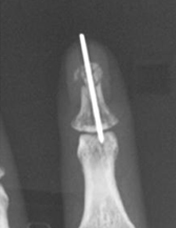

Distal falanks, parmak ucundaki kemiktir. Uygun parmak fonksiyonu ve tırnak büyümesi için sabit bir distal falanks gerekir. Çoğu distal falanks kırığının düzeltilmesi gerekmezken, bazılarının düzeltilmesi gerekir. Bunlar, düzgün bir şekilde birleştirilmesi gereken birçok parça ile oldukça karmaşık olabilir. Kötü bir şekilde düzeltilmiş kırıklar iyi iyileşmez, çok fazla ağrıya neden olur ve işe dönüşü geciktirir.

Eldeki kapalı kırıklar, yerinden oynamışsa veya deformiteye neden oluyorsa, uygun hizaya geri konulmalı ve ele iyi bir fonksiyon kazandırmak için metal teller, vidalar veya plakalarla sabitlenmelidir. Bu, el yaralanmasından birkaç gün sonra, mümkün olan en kısa sürede erken rehabilitasyona izin vermek için en iyi şekilde yapılır.